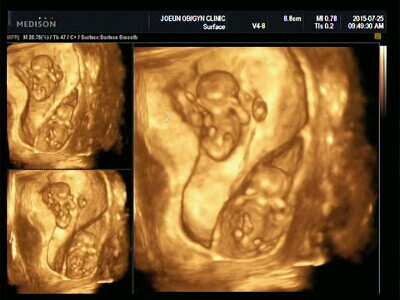

하지만 아쉬움은 오래가지 않았어요..2주 후 다시 찾은 병원에서

어? 아기집이 하나 더 있네요? 쌍둥이인데요?

- 1.8키로..도담이

폐가 펴지지 않은 채로 태어나 호흡이 어려웠던 도담이.

얼굴과 몸에 부착된 수많은 기계들 탓에 일주일 정도 얼굴을 제대로 볼 수가 없었어요

- 2.0키로..랄라

기특하게도 숨도 잘 쉬어 주었고, 몸무게가 너무 작다는 것 외에는 큰 이상이 없었죠

그 와중에 아가들 초음파사진 넘 이쁘게 나온 것 같아요^^ 저는 울쌍둥이 콩모양으로 된 것만 봤는데 ㅋㅋㅋㅋㅋ

둥이는 초음파 사진에 함께 담을 수 있는 시기가 너무 잠깐이라 참 아쉽죠.. 킴쑤님네 둥이는 일란성인가요?